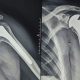

SIRACUSA – Tre focus dedicati alla chirurgia protesica articolare che continua a compiere importanti passi in avanti grazie all’utilizzo di metodi e...